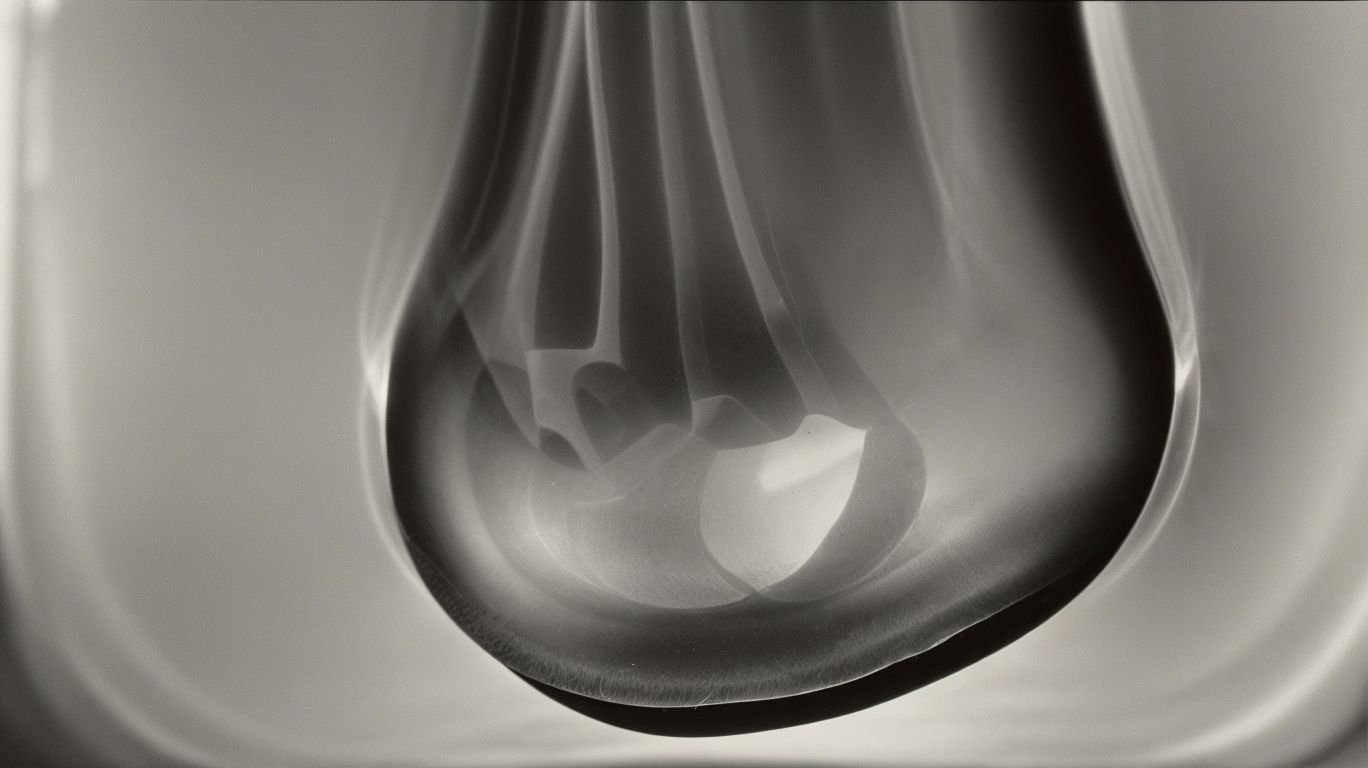

Navicular cysts in horses refer to fluid-filled sacs that develop in the navicular bone, a critical structure in the horse’s foot, leading to lameness and discomfort.

Diagnosing navicular cysts in horses involves a comprehensive approach, including physical examination, X-rays, and ultrasound imaging to assess the structural integrity and potential cystic formations in the navicular region.

X-rays play a pivotal role in visualizing bony changes, fragmentations, and potential cysts within the navicular bone. They enable detailed assessment of the bony structures and any irregularities that may signify the presence of navicular cysts.

X-ray imaging plays a crucial role in diagnosing navicular cysts in horses, enabling veterinarians to visualize bone structures and identify potential cystic formations in the navicular region.

By utilizing X-ray technology, veterinarians can accurately assess the extent of the navicular cysts and any associated bone abnormalities, aiding in the formulation of a targeted treatment plan.